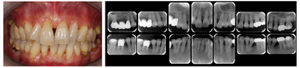

図8 長期メインテナンスの実際

1999年初診。年齢32歳 女性、“はぐきが腫れる”という主訴で来院されました。若い年齢にもかかわらず重度歯周炎にすでに罹患をしていました。

治療後21年。右上第1大臼歯は治療時に抜歯となってしまいましたが、治療完了後は定期メインテナンスを継続し、歯周組織は安定、一本の歯も失わずに現在まで経過しています。